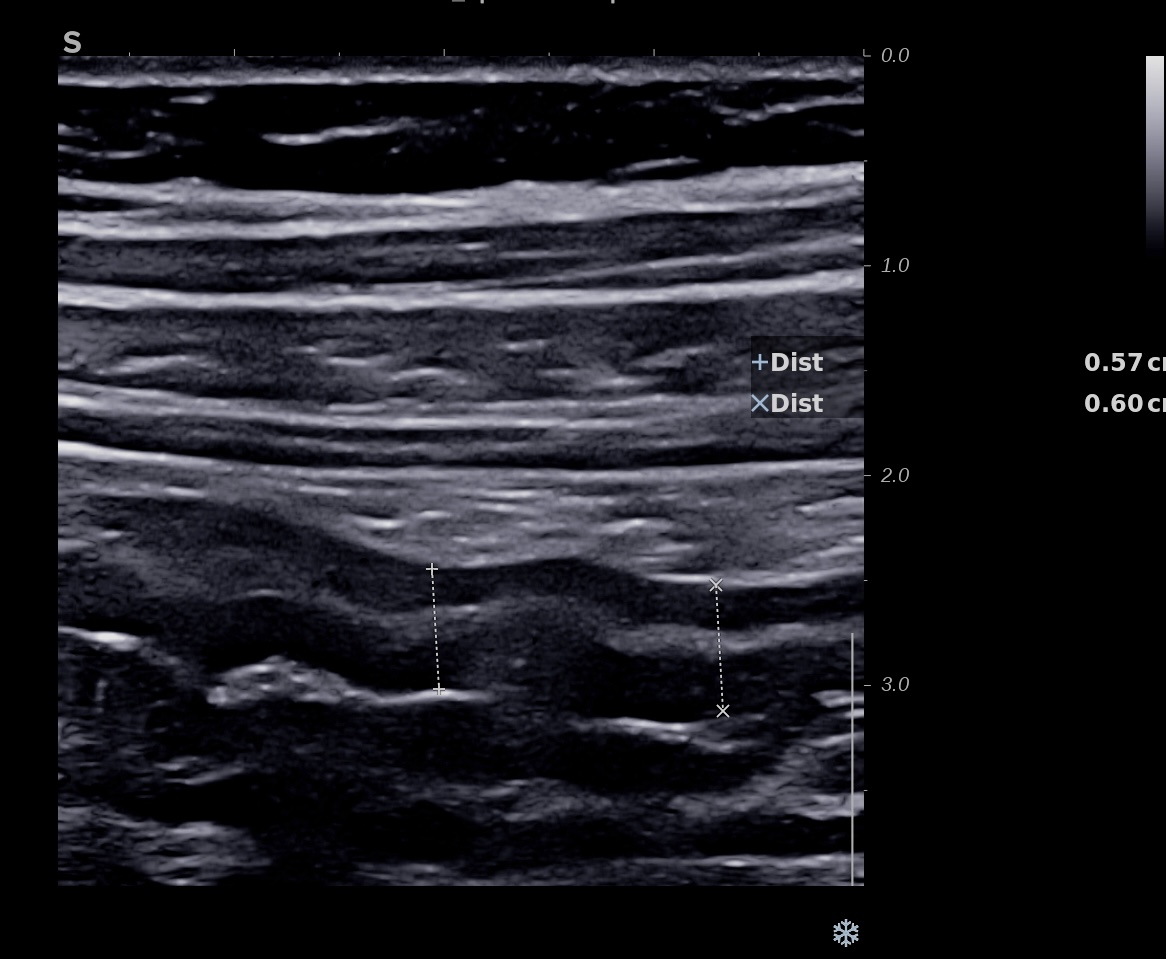

Epaississement considérable par endroit (10 ou 11 mm), disparition totale de la structure en couches, déformation de la surface avec ulcérations, déformation des contours, infiltration de la graisse, hyperactivité Doppler

Le Score de Milan (MUC) est à 17.4

une inflammation au delà de 8 mm, voir 10 ou exceptionnellement 12 mm est un signe de gravité.

2. la disparition de la structure en couches

L’inflammation qui dans la RCH est au départ superficielle (couches 2 et 3) gagne la totalité de la paroi (la sous muqueuse devient hypoéchogène et toute la paroi devient noire hypoéchogène)

Si l’inflammation s’aggrave, on peut voir des ulcères creusants en surface et la limite externe de l’anse (classiquement rectiligne dans la RCH) devient irrégulier, bosselé.